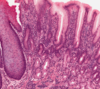

Straight tubular glands (like test tubes in a rack). You don’t really find Paneth cells as a general feature. There’s a smooth surface epithelium

colon